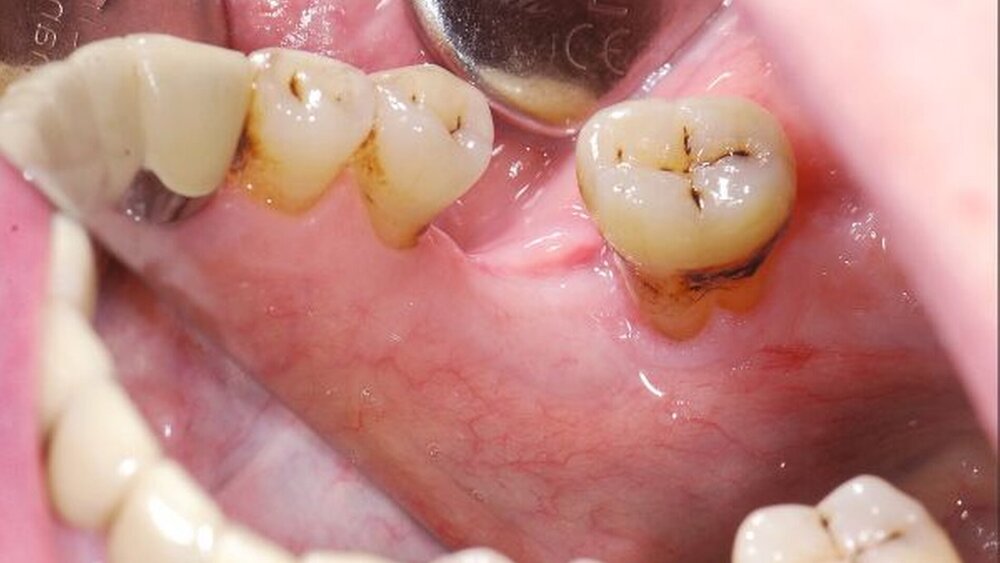

Ein 81-jähriger Patient wurde der Klinik aufgrund eines Ulkus im Molarenbereich des linken Unterkiefers vorgestellt. Klinisch zeigte sich hier eine spontane, schmerzlose Knochenexposition von Regio 36 bis nach retromolar. Der parodontal geschädigte Zahn 37 lag im Zentrum der Läsion (Ab- bildung 1). Die klinische Morphologie war nicht richtungsweisend, insbesondere fanden sich keine umgebenden Vorläufer- läsionen, kein Randwall und keine pathologischen Gefäßektasien als typische Stigmata einer malignen Läsion, aber auch keine Hinweise auf eine traumatisch-irritative oder infektiöse Ursache. Sowohl 37 als auch die Prämolaren des linken Unterkiefers reagierten auf Kälte-Provokation sensibel.

Damit war eine kausale Lokaltherapie nicht erforderlich, sondern es konnte die spontane Rückbildung nach der vollständigen hämatologischen Remission abgewartet werden. Zur histologischen Absicherung bei dieser „nicht chirurgischen“ Therapie wurden Biopsien aus der Ulkuszone gewonnen. Hierbei ergab sich lediglich Entzündungs-gewebe mit Plattenepithelhyperplasien und nekrotischem Knochengewebe. Im Verlauf bildete sich die Läsion allein unter lokaler Wundpflege spontan zurück (Abbildung 2) und heilte schließlich innerhalb von neun Wochen vollständig ab (Abbildung 3).